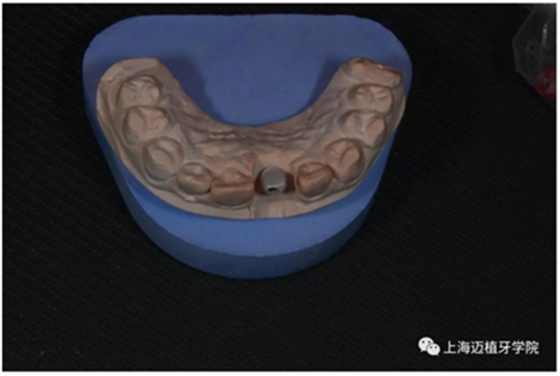

取工作模型

非工作模型